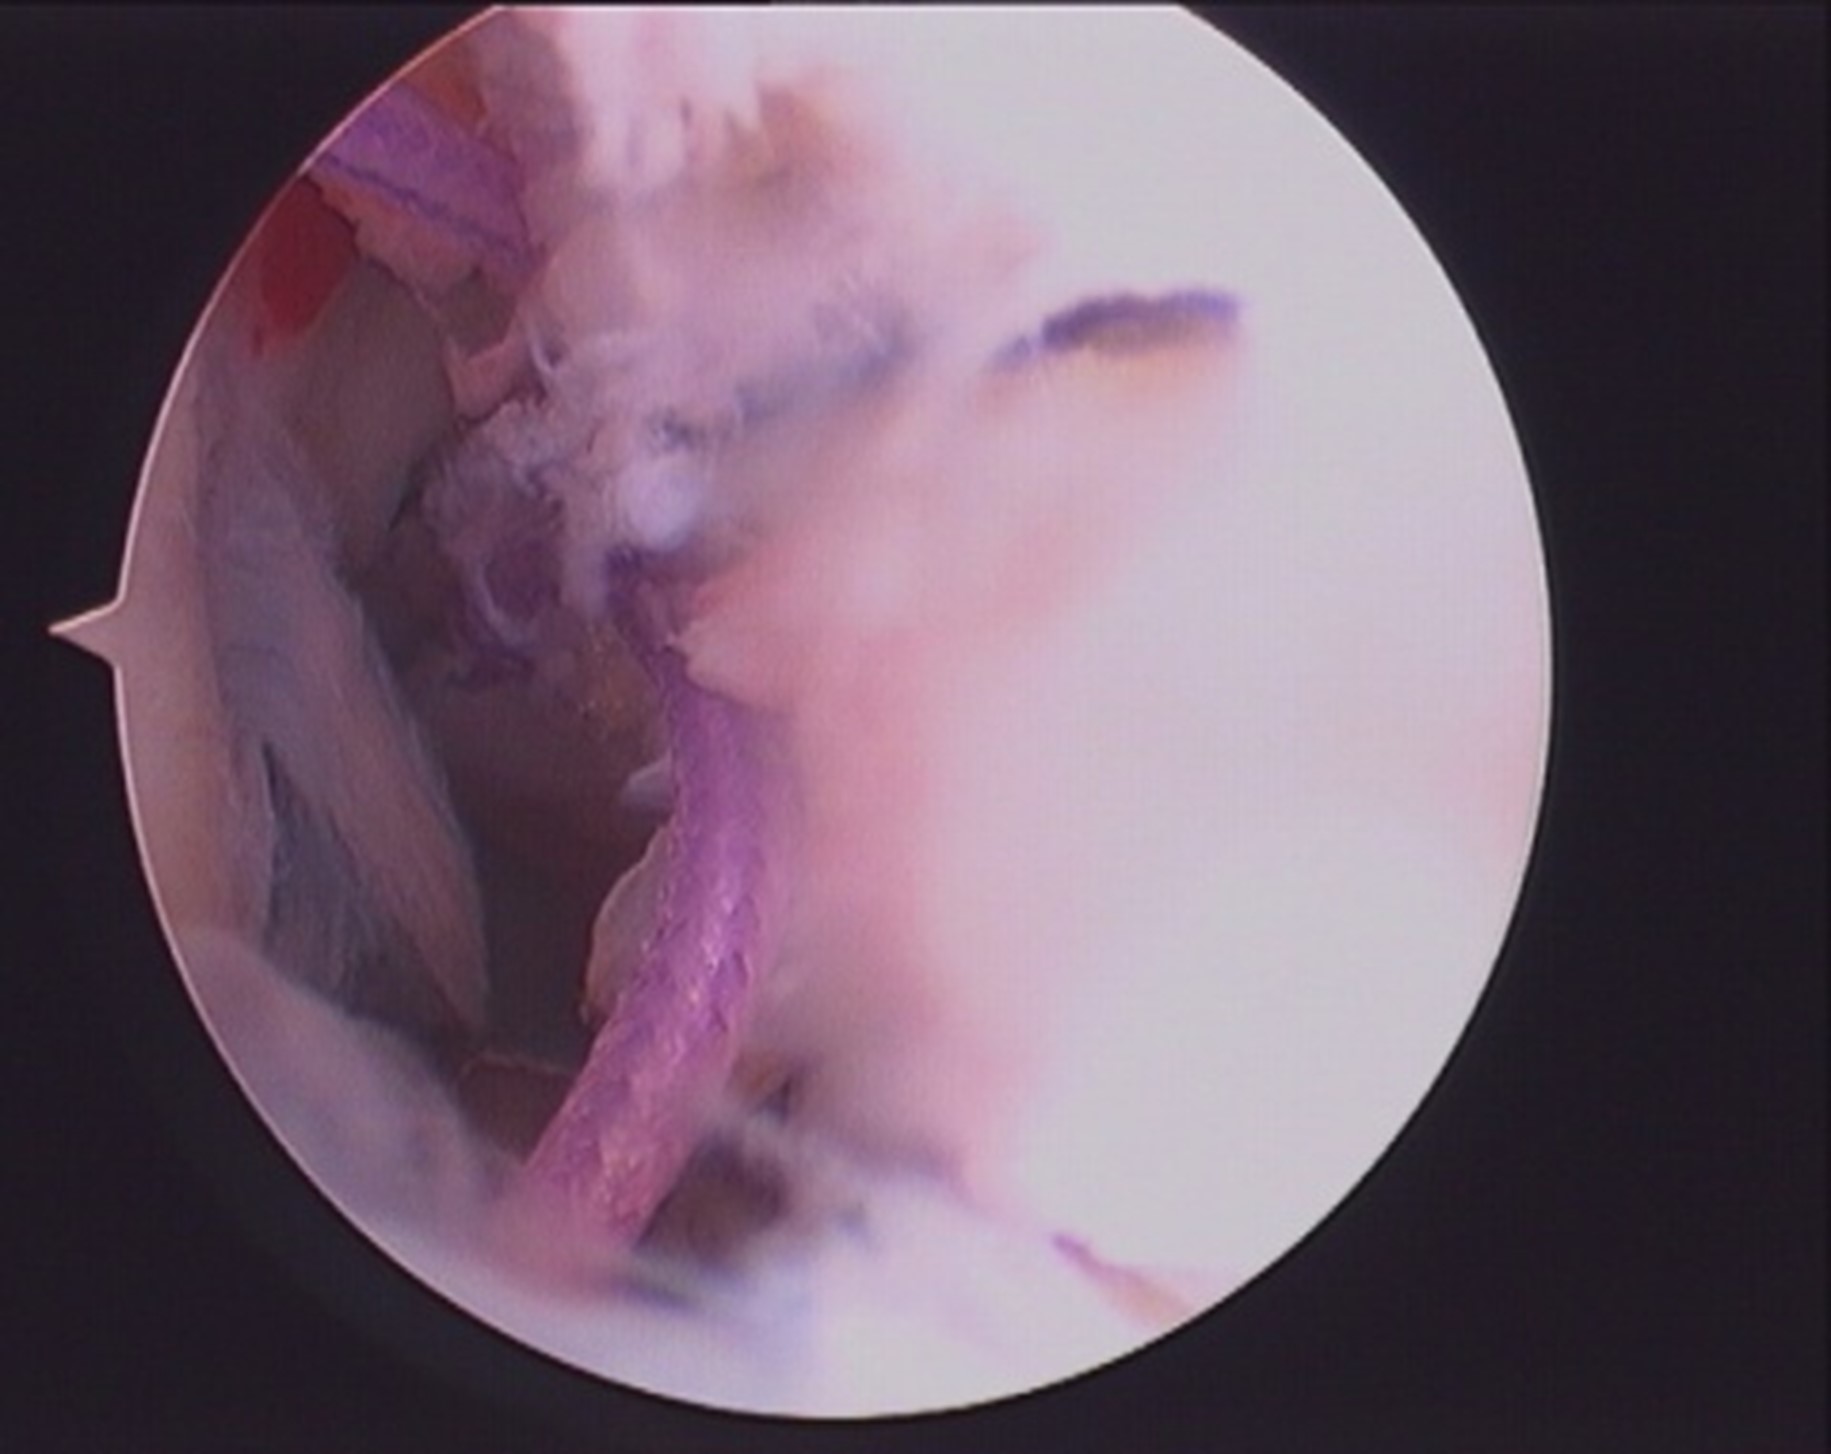

- PCL is wrapped with suture loop (Arthrex fibrewire no 2/orthocoat) by passing the suture ends from both windows(bare area in between ACL and PCL,area between medial femoral condyle and PCL).fig 1,2.

- Both ends of the suture loop are delivered posteriorly through inferior PM portal and sliding knot is passed and sitted over the osseo-ligamentous fragment.fig 3, 4.